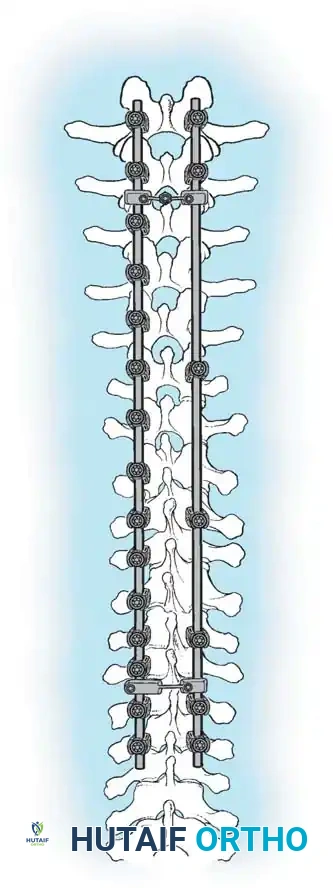

The posterior approach to the spinal column remains the most universally utilized and versatile corridor for the surgical management of adolescent idiopathic scoliosis (AIS). Familiar to all fellowship-trained orthopaedic spine surgeons, this extensile approach offers safe, comprehensive exposure of the entire vertebral column. It facilitates the application of modern multi-segmental pedicle screw constructs, allows for aggressive posterior column osteotomies, and provides a massive surface area for robust arthrodesis.

The long-term success of any operative procedure for scoliosis is fundamentally predicated on achieving a solid, mature arthrodesis. While instrumentation provides immediate biomechanical stability and deformity correction, it is the biological fusion that ensures lifelong maintenance of alignment.

PRINCIPLES OF POSTERIOR SPINAL ARTHRODESIS

The ultimate goal of scoliosis surgery is not merely instrumentation, but a solid, lifelong arthrodesis. The classic extra-articular Hibbs technique has largely been abandoned in favor of comprehensive intra-articular fusion techniques that incorporate the facet joints.

2. Biomechanical Stability: Rigid segmental instrumentation to neutralize micromotion.

Modern literature, including landmark studies by Betz et al., has demonstrated that the rigid fixation provided by contemporary multi-segmental pedicle screw constructs, combined with aggressive facetectomy and the inherent osteogenic potential of the immature adolescent skeleton, yields excellent fusion rates using local autograft (bone harvested from the spinous processes and osteotomies) supplemented with allograft.